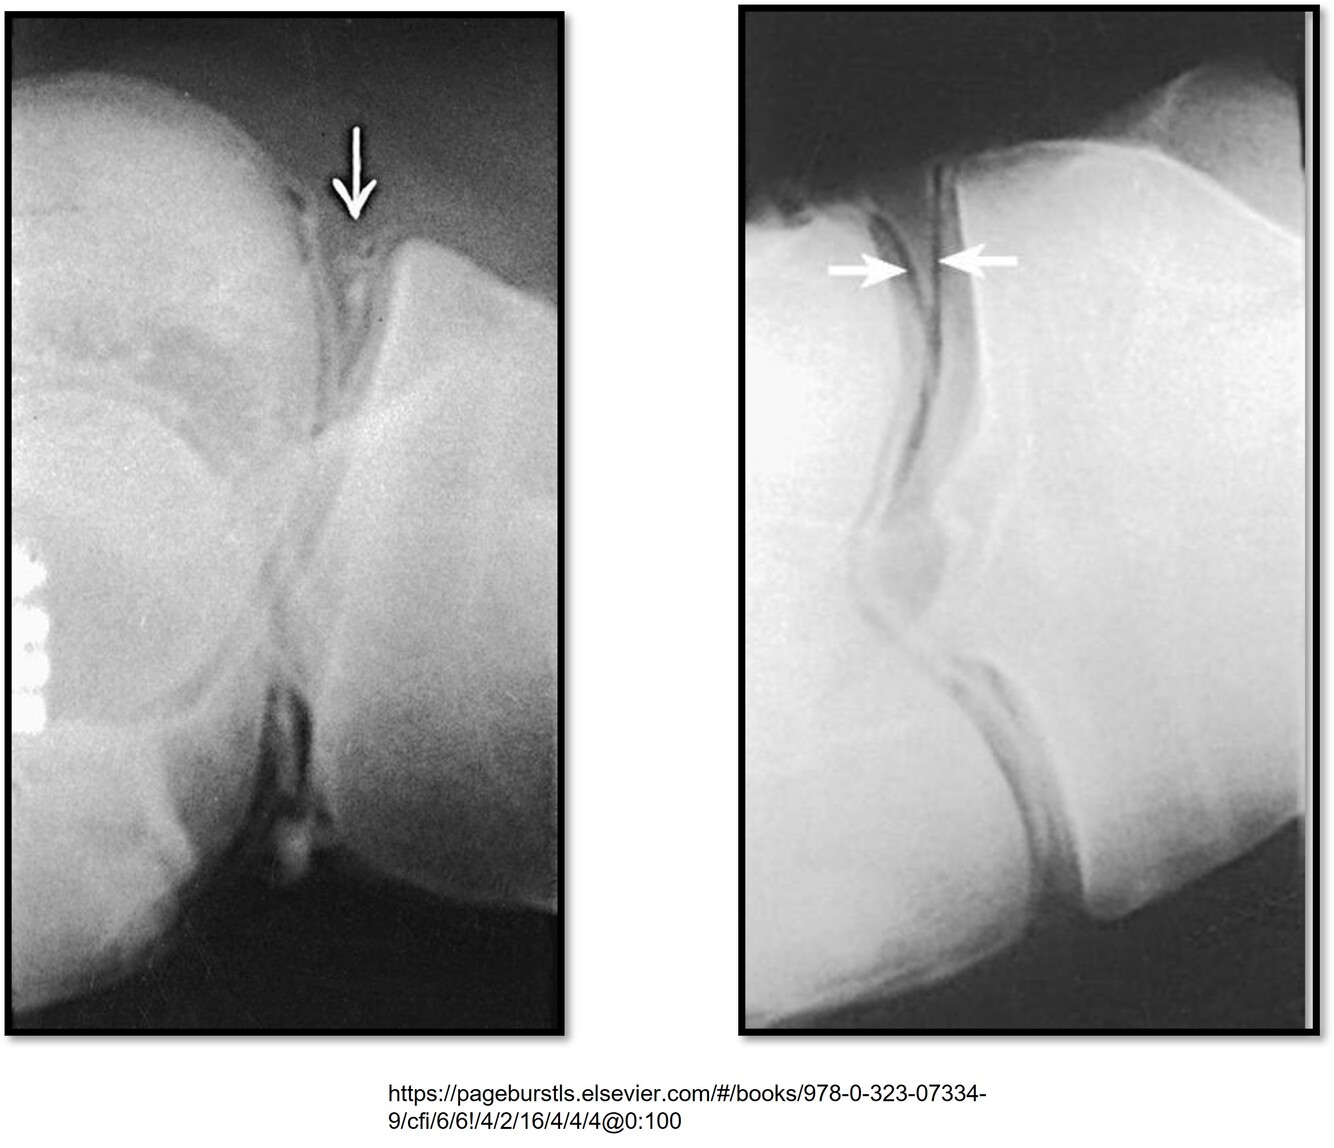

A torn vs. healthy meniscus

What pathology is this showing?

Q